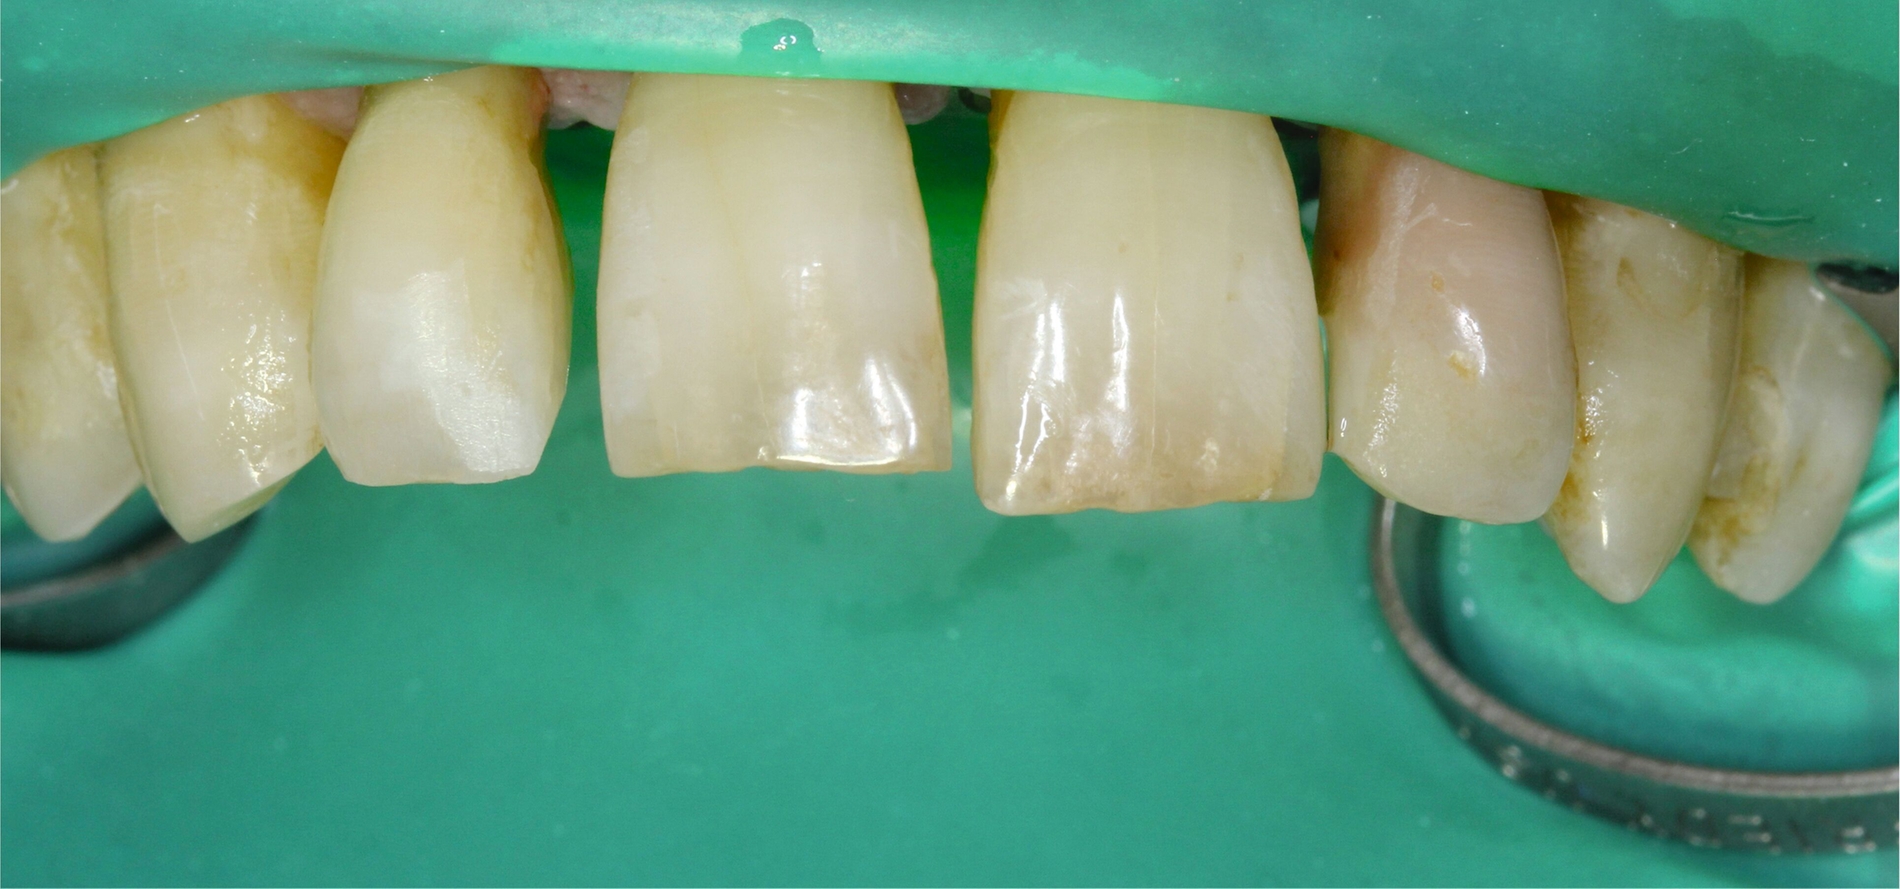

Entsprechend der hier aufgeführten schwachen wissenschaftlichen Evidenz lässt sich schlussfolgern, dass Zähne mit einem Lockerungsgrad II oder höher möglicherweise von einer Schienung vor regenerativen parodontalchirurgischen Eingriffen profitieren können [Cortellini et al., 2001]. Diskutiert wird in diesem Zusammenhang die Förderung der Stabilität des Blutkoagulums durch die Reduktion der Mobilität der Zähne in der Heilungszeit. Nicht zuletzt kann durch eine Schienung das aufgrund der Mobilität mögliche sekundäre okklusale Trauma reduziert beziehungsweise eliminiert werden. In diese Schienungen wird in der Regel jeweils ein benachbarter Zahn ohne erhöhte Mobilität einbezogen. Zwei verschiedene Schienungen zur Reduktion der Mobilität im Rahmen der regenerativen Parodontalchirurgie sind in den Abbildungen 3 und 4 dargestellt.